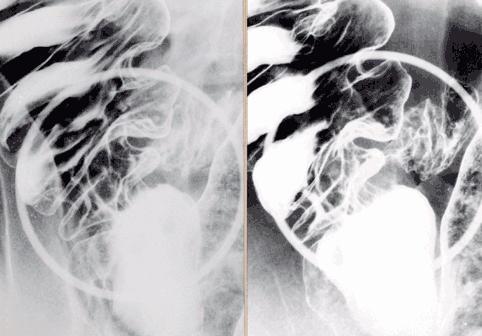

Amebic colitis which mainly involved the cecum and rectum.

Inflammatory or ulcerative disease / lesions/Amebiasis

Location

Large intestine(Colon)/Ilenocecal region

Technique, Method

X-ray